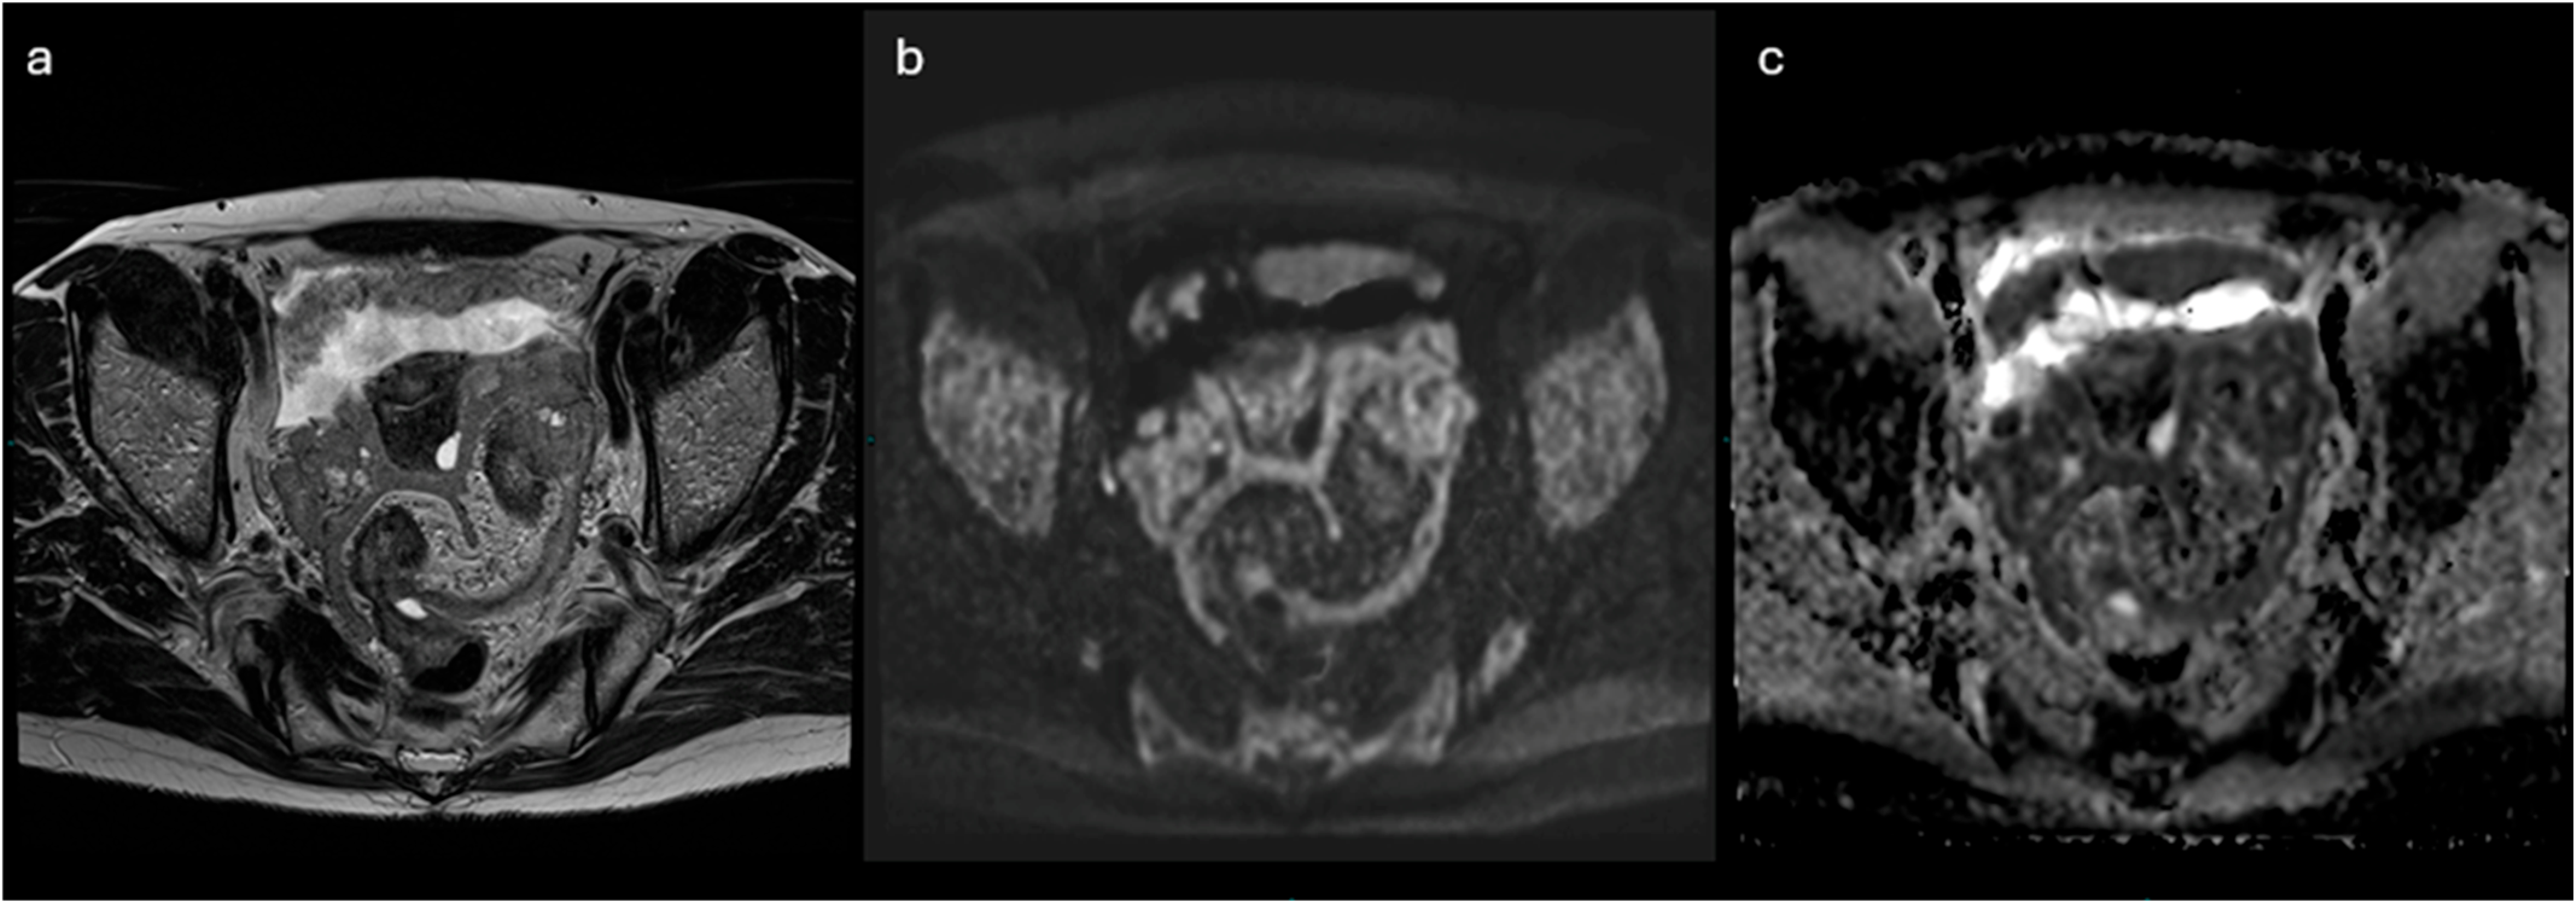

2.3. MRI

2.3.1. ADNEX-MR Scoring System

2.3.2. O-RADS MRI Score

- Lesions with solid tissue (excluding solid lesions described in score 2) showing type 2 enhancement curve (intermediate risk; Figure 5)

3.1. O-RADS MRI/ADC Score

- Thomassin-Naggara, I.; Poncelet, E.; Jalaguier-Coudray, A.; Guerra, A.; Fournier, L.S.; Stojanovic, S.; Millet, I.; Bharwani, N.; Juhan, V.; Cunha, T.M.; et al. Ovarian-Adnexal Reporting Data System Magnetic Resonance Imaging (O-RADS MRI) Score for Risk Stratification of Sonographically Indeterminate Adnexal Masses. JAMA Netw. Open 2020, 3, e1919896. [Google Scholar] [CrossRef]

- Rizzo, S.; Cozzi, A.; Dolciami, M.; Del Grande, F.; Scarano, A.L.; Papadia, A.; Gui, B.; Gandolfo, N.; Catalano, C.; Manganaro, L. O-RADS MRI: A Systematic Review and Meta-Analysis of Diagnostic Performance and Category-wise Malignancy Rates. Radiology 2023, 307, e220795. [Google Scholar] [CrossRef]

- Sadowski, E.A.; Thomassin-Naggara, I.; Rockall, A.; Maturen, K.E.; Forstner, R.; Jha, P.; Nougaret, S.; Siegelman, E.S.; Reinhold, C. O-RADS MRI Risk Stratification System: Guide for Assessing Adnexal Lesions from the ACR O-RADS Committee. Radiology 2022, 303, 35–47. [Google Scholar] [CrossRef]

- Manganaro, L.; Ciulla, S.; Celli, V.; Ercolani, G.; Ninkova, R.; Miceli, V.; Cozzi, A.; Rizzo, S.M.; Thomassin-Naggara, I.; Catalano, C. Impact of DWI and ADC values in Ovarian-Adnexal Reporting and Data System (O-RADS) MRI score. Radiol. Med. 2023, 128, 565–577. [Google Scholar] [CrossRef]